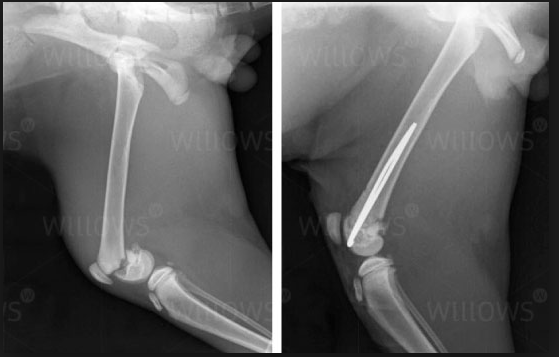

Please look below at all these x-rays from last years random friend’s injuries ( and these are without even searching as these happen all the time). If it is not a growth plate , it is a neck, back, wrist, hock, ribs or any large bones for that matter. One of the most common example is when a small piece of the knee joint splits, which end up in a 2-3000€ surgery. I do not see much point in taking such a huge risk, so don’t run adults and pups! Period!

Here is the proof! More info after the pictures!

• A portion of the growth plate may remain functional (open) and thus the bone and limb becomes twisted

• In the front limb where the bones are paired (radius and ulna) the limb may become twisted at the wrist (carpus)

Surgery • Surgery is generally done as soon as possible after this type of injury occurs.

• Generally pins are used to repair these types of fractures if a type 1 or 2 fracture occurs.